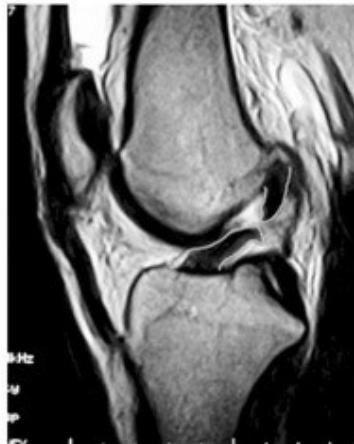

MRI (Gold Standard)

- Best imaging modality for ACL injuries

MRI Findings:

- Normal ACL

- Torn ACL